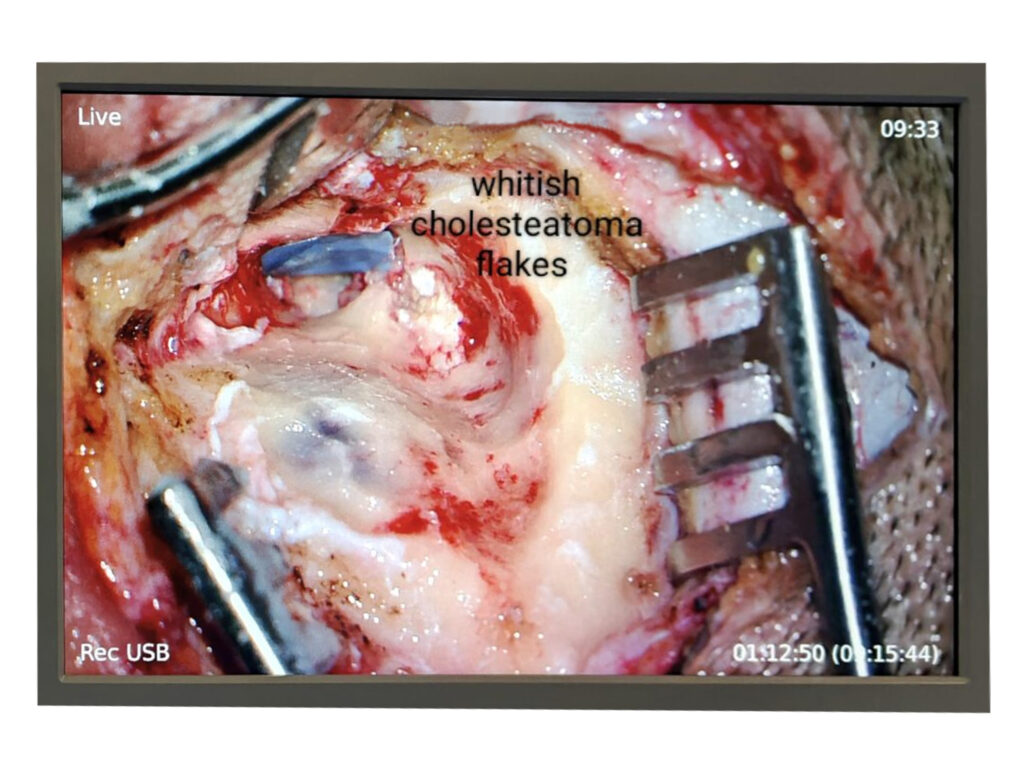

Whitish Cholesteatoma Flakes

Cholesteatoma of the Ear

Tympanomastoidectomy Surgery